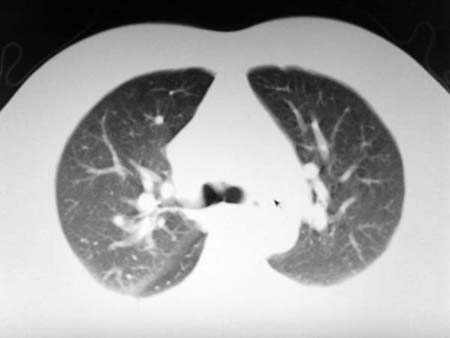

以下是引用qian在2008-4-27 17:02:00的发言:[br]考虑右下肺肺段隔离症伴有感染,建议做增强看看。

以下是引用zsl6918在2008-4-27 17:13:00的发言:[br]考虑右肺下叶炎性病变可能性大,建议抗炎治疗后复查,现有资料不能完全除外肺癌可能。